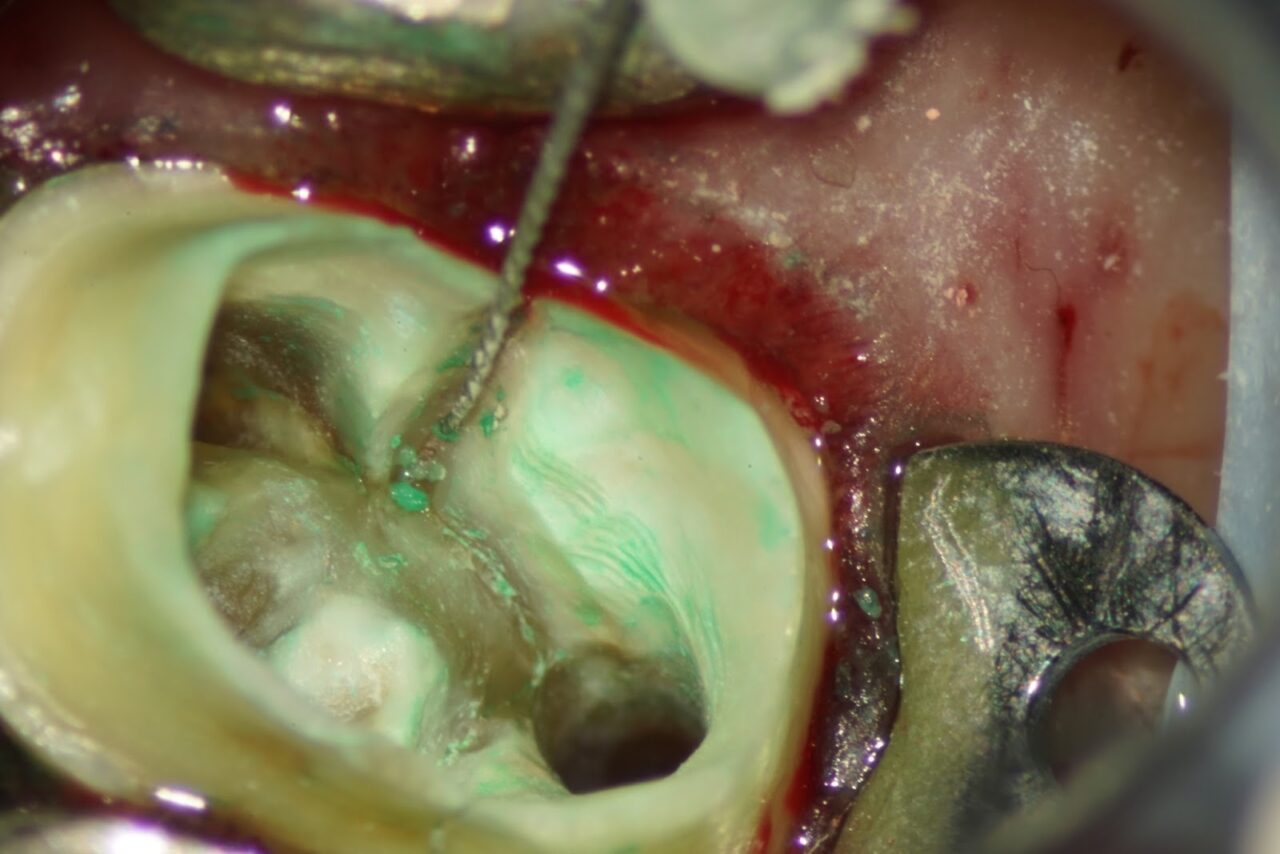

スーパーボンドという日本製の接着剤を用いて破折の接着を行います。

その後にフローレジンにて歯の強度を高めるために隔壁を兼ねたレジン隔壁を作ります。

次回より本格的な根管治療を行うための準備をしました。CTで根管の内容物がきちんと取り除かれている事が確認できれば、次回はバイオセラミックを用いた根管充填になります。